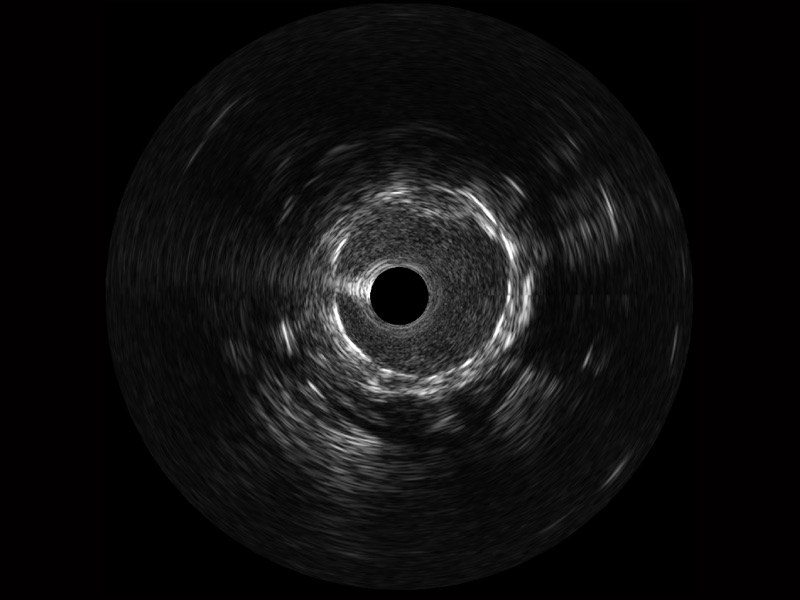

传统IVUS图像

对比传统IVUS导管成像,狗万官方网站宽频IVUS图像的近场支架梁显影更细腻,远场中膜外血管仍清晰可辨,兼顾远中近,兼顾分辨力与穿透深度